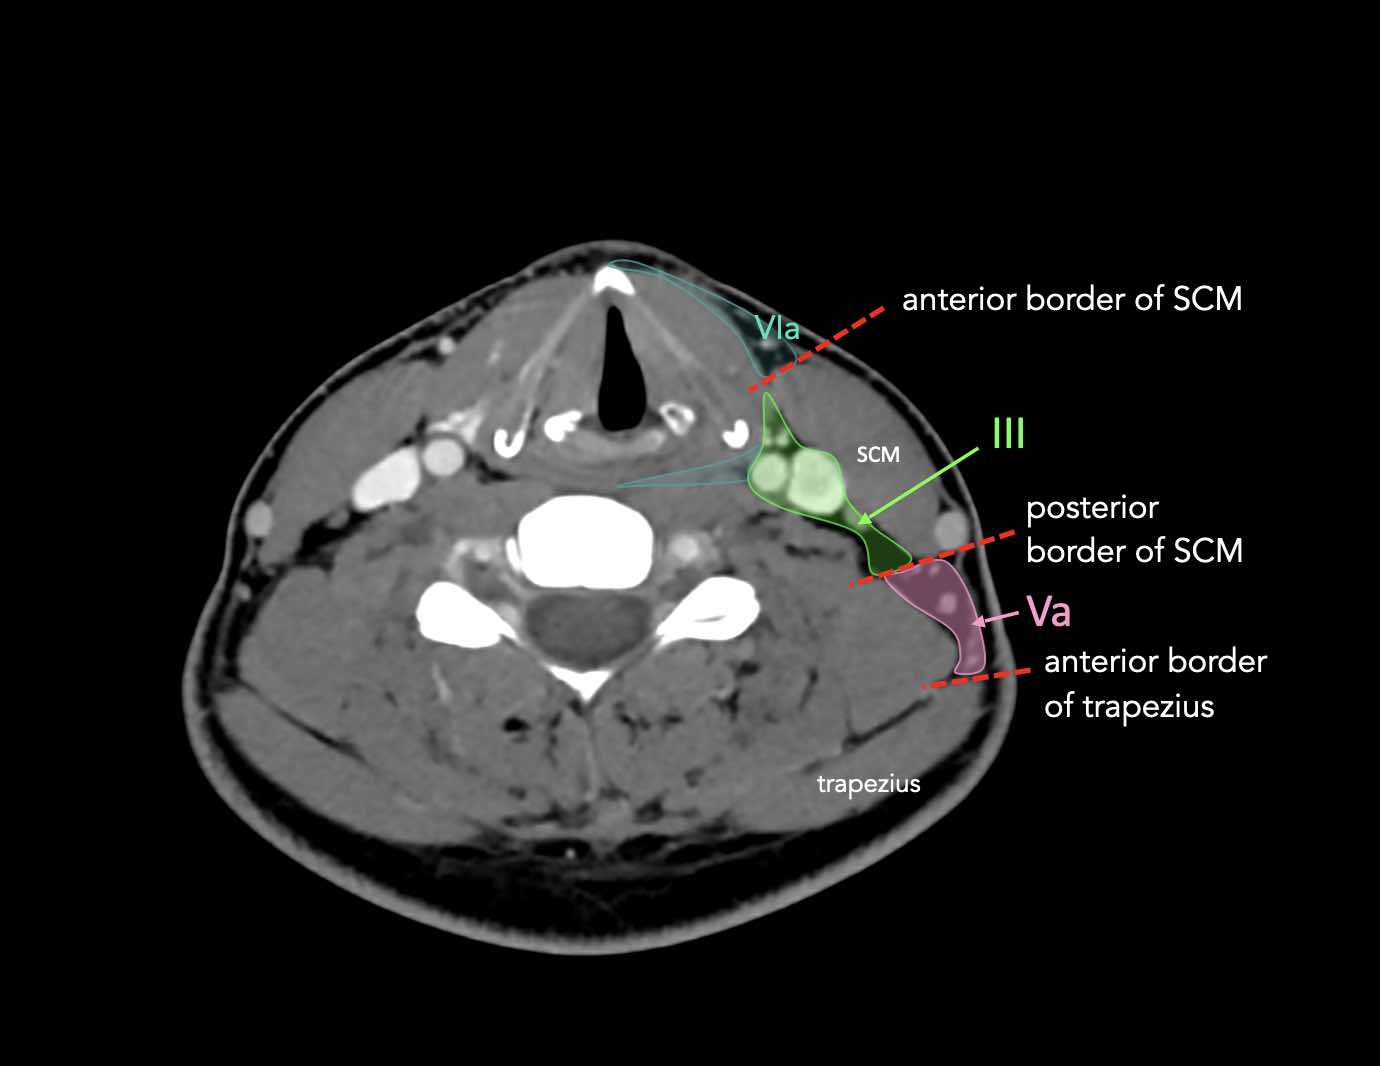

CT Scan Mặt Cắt Ngang (Axial CT)

Các lát cắt CT mặt phẳng ngang tương ứng với hình minh họa tổng quan.

Các lát cắt CT mặt phẳng ngang với hình ảnh chi tiết hơn.

Nhấp vào hình ảnh để phóng to.

II – Tĩnh mạch cảnh trên

Tầng II có thể được chia thành tầng IIa và tầng IIb bằng cách vẽ một đường tại bờ sau của tĩnh mạch cảnh trong.

Các hạch bạch huyết ở tầng IIa và IIb có nguy cơ chứa di căn từ các ung thư hốc mũi và khoang miệng, vòm hầu, hầu miệng, hạ hầu, thanh quản và các tuyến nước bọt lớn.

III – Tĩnh mạch cảnh giữa

Các hạch bạch huyết ở tầng III có nguy cơ chứa di căn từ các ung thư khoang miệng, vòm hầu, hầu miệng, hạ hầu và thanh quản.

V – Tam giác cổ sau và hố thượng đòn

Tầng V chứa các hạch của nhóm tam giác cổ sau nằm ở phía sau cơ ức đòn chũm, xung quanh phần dưới của thần kinh phụ gai sống và các mạch máu cổ ngang.

VI – Cổ trước